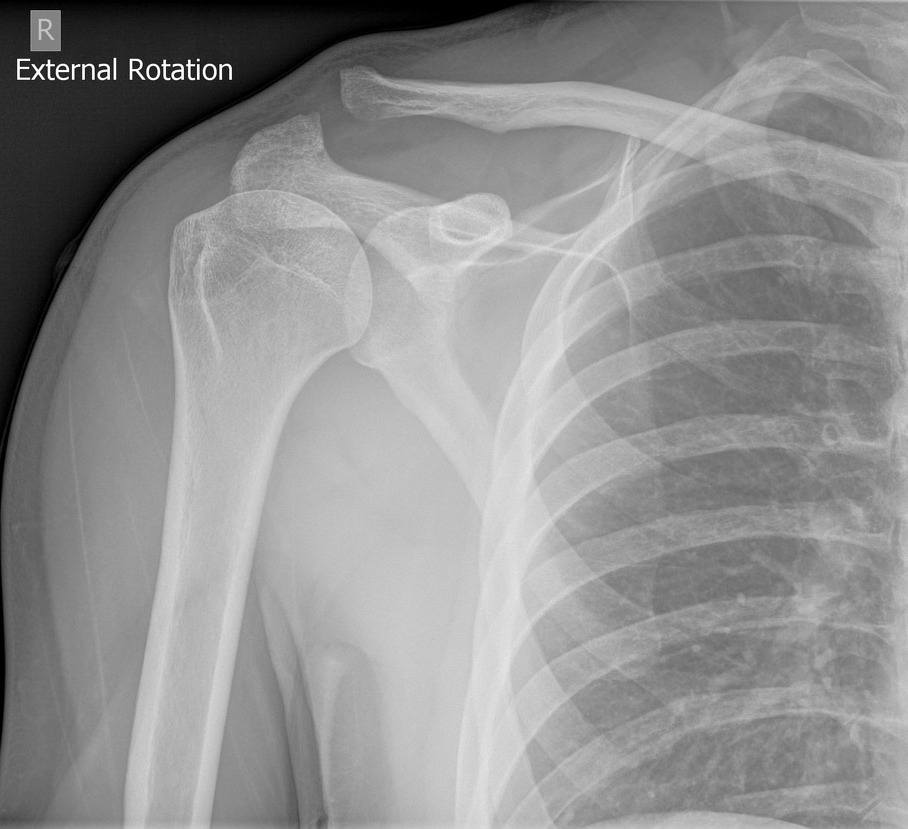

Trật khớp cùng đòn

» Thông tin: Nam giới – 30 tuổi.

» Lâm sàng: Chấn thương khớp vai.